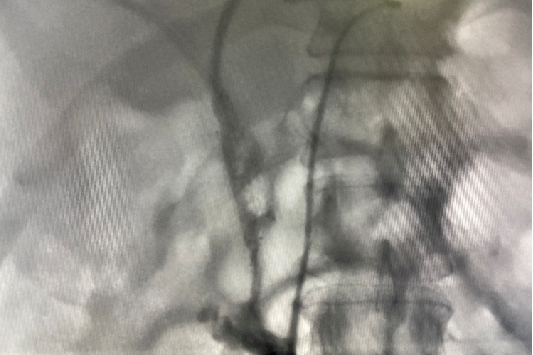

术后1月复查:右胆管残留狭窄、造影剂线形通过,考虑患者目前无明显黄疸症状,肿瘤较前有所缓解,为改善生活质量,给予拔除